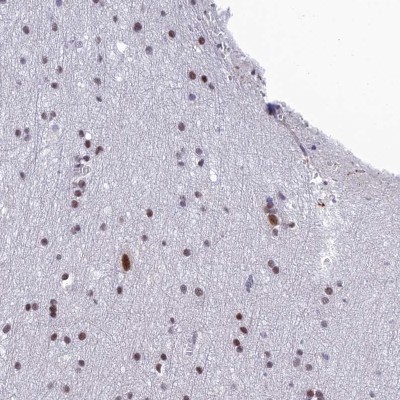

- Experimental details

- Immunohistochemistry-Paraffin: RSRC1 Antibody [NBP1-90756] - Staining of human cerebral cortex shows high expression.